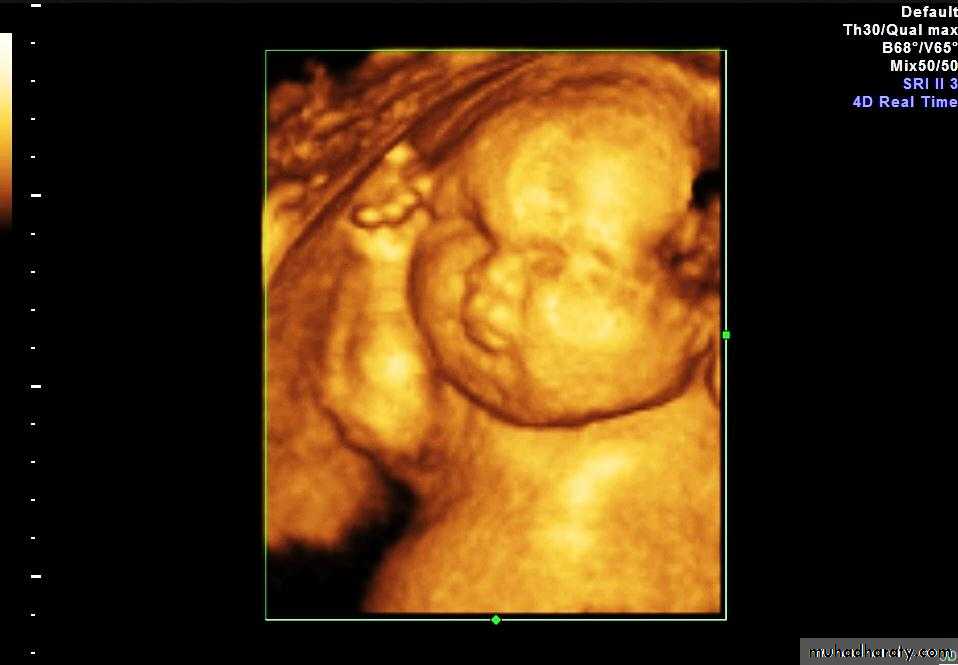

Anenecephaly >>>> frog sign appearance :

Anencephaly is the most severe form of cranial neural tube defect (NTD) and is characterized by absence of cortical tissue (although brainstem and cerebellum may be variably present) as well as absence of the cranial vault.Associations

Anencephaly may be sonographically detectable as early as 11 weeks. Ultrasound can be a non invasive,

no parenchymal tissue is seen above the orbits and calvarium is absent: parts of the occipital bone and mid brain may be present urinary tract abnormalities: hydronephrosis most common